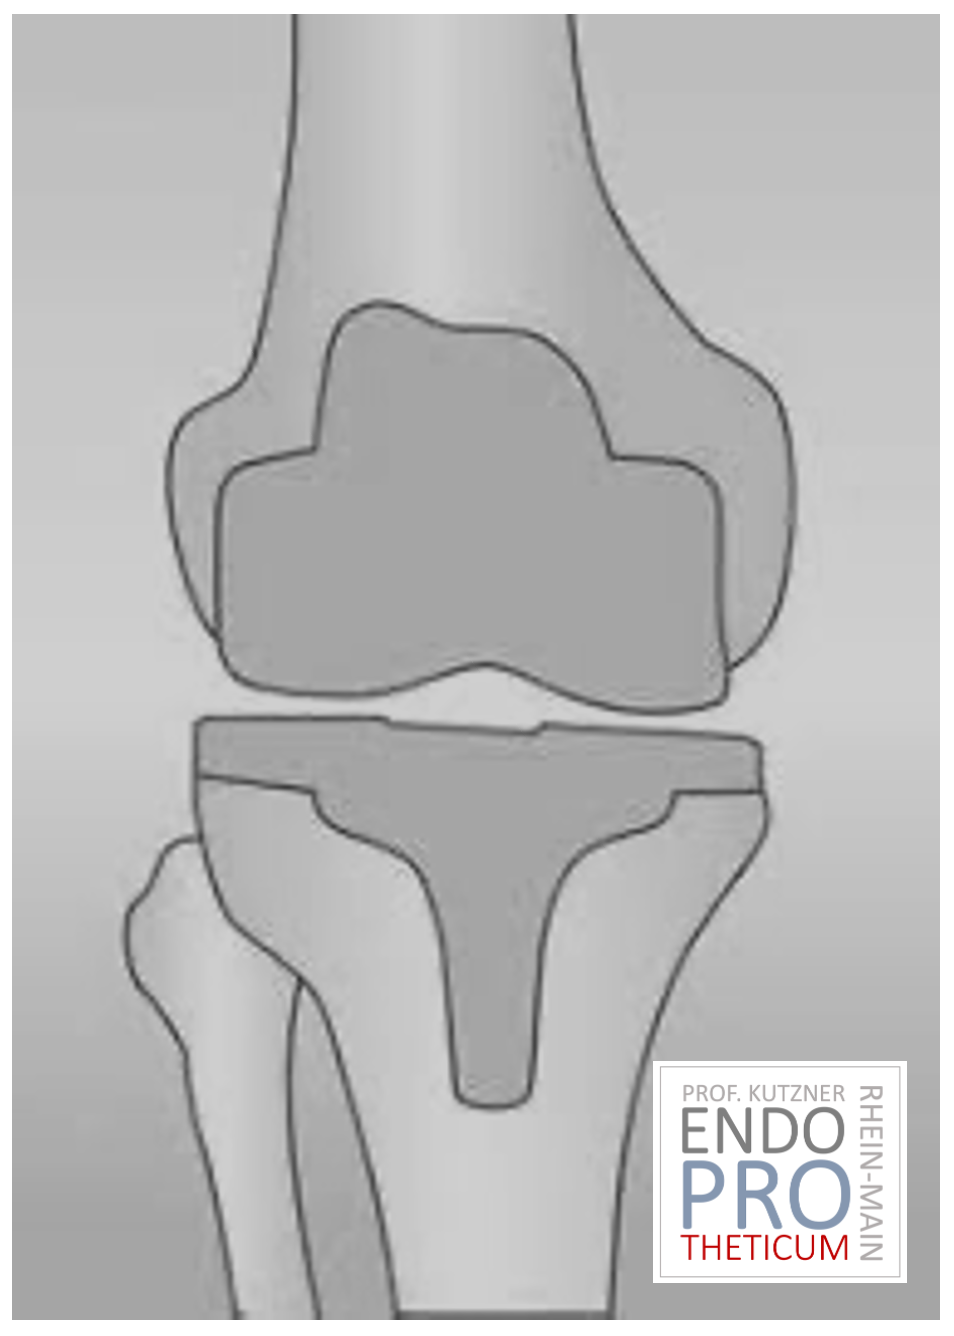

- استبدال كامل للسطح الأسمنتي (الكلاسيكي: " الركبة الاصطناعية ")

يحل مفصل الركبة الاصطناعي محل سطح الغضروف الذي دمره التهاب المفاصل العظمي.

يظل العظم الأساسي في عظم الفخذ والرأس الظنبوبي سليمًا. يقارن البعض مفصل الركبة الاصطناعي الحديث بتتويج الأسنان، والمصطلح الدقيق هو ما يسمى

إعادة تسطيح اللقمتين. بين الأسطح الجديدة في الجزء العلوي والسفلي من الساق يوجد ما يسمى بالبطانة المصنوعة من البلاستيك الأبيض المقوى خصيصًا، والتي يمكن رؤيتها في صورة الأشعة السينية على أنها المسافة بين الأجزاء المعدنية.